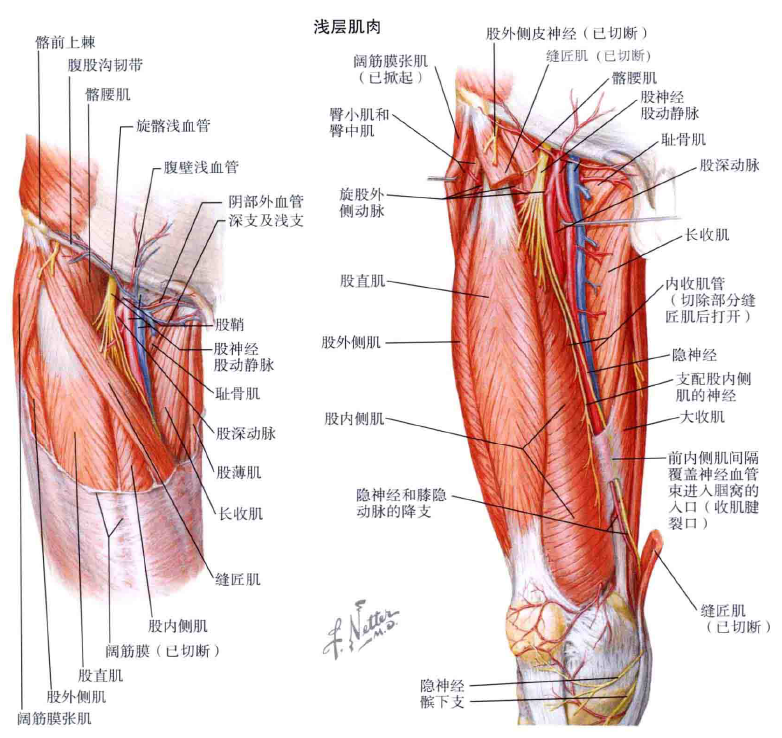

其次,大家可以看看髋关节周围重要的肌群、血管神经:

右侧髋关节-前方-浅层重要肌群及血管神经

右侧髋关节-前方-深层重要肌群及血管神经